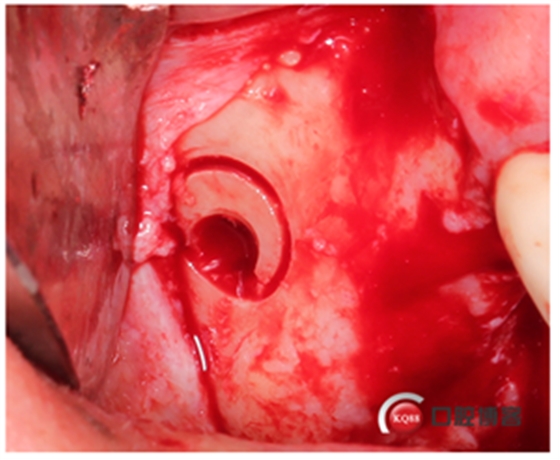

這時候我還沒有開窗,還沒有用器械剝離竇膜,但頰側(cè)骨壁和上頜竇膜已經(jīng)水壓撥開了。接下來我再開窗是不是就安全多了?看起來這種環(huán)切鉆挺嚇人的,那么鋒利的鋸齒。不要擔(dān)心了,這么多病例了,沒有一例在開窗時會撕裂膜的。當(dāng)然技巧還是有的,記得要反轉(zhuǎn),轉(zhuǎn)速200-500轉(zhuǎn),放心,切割能力一樣強大,4-6秒就可以磨下去。

看起來是不是像個藝術(shù)品?哈哈,自娛自樂一下,別見笑。

取下骨片,這才叫開窗了。